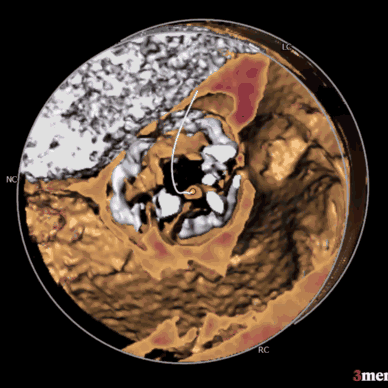

左冠开口高度12.0mm,右冠开口高度17.8mm,左冠高度较低,根据瓦氏窦内径和瓣叶长度综合判断,左冠存在较高堵塞风险;左室腔增大,心室壁未见明显增厚。

②患者左冠瓣冗长,结合瓦氏窦内结构,存在较大左冠封堵危险;

①患者左窦瓣叶明显长于左冠开口,窦部偏小,人工瓣膜打开后左冠闭塞风险较大大,需制定冠脉保护策略。

在术前评估阶段,首先通过心电图及超声探查,对患者心力储备、心脏电生理状况有了一个基本的把握,明确了患者自身的完全左束支传导阻滞,以及低 LVEF 情况。之后的 CTA 评估,通过瓣环上平面测量,提示了瓣叶较大冗长,上缘延展于 STJ 平面以上。于术前明确了冠脉极高闭塞风险,指示术中球囊预扩时,除常规 Balloon sizing 再次确认瓣膜型号外,还应当着重观察左冠灌注情况。